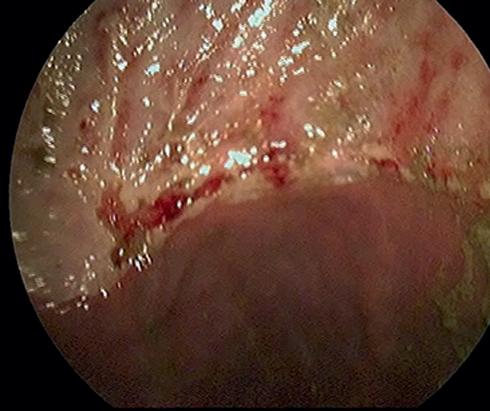

Diagnosis relies on visualisation of ulcers in the stomach region, and this is achieved with the use of a Gastroscope.

The apparatus is a three-metre-long flexible tube that is passed down the oesophagus via the nostril.

Acamera on the end of the scope is used to view the inside of the stomach, with the Gastroscope being connected to a computer screen.

AGastroscope gives us the ability to view the squamous, glandular and pyloric regions

of the stomach - all common areas for ulcers. During your horse’s scope, the vet can take video or photos of any area of interest. Prior to scoping, your horse's stomach will need to be empty, therefore fasting is carried out from the previous evening.

Asedative is used to help keep your horse relaxed and comfortable - the procedure is not painful but it can be a little unfamiliar for your horse.

Diagnosis of ulcers in the stomach region is achieved with the use of a Gastroscope.

AGastroscope examination of your horse’s stomach can provide quick information for treatment of gastric ulcers.